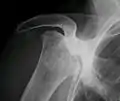

Radiography of total avascular necrosis of right humeral head. Woman of 81 years with diabetes of long evolution.